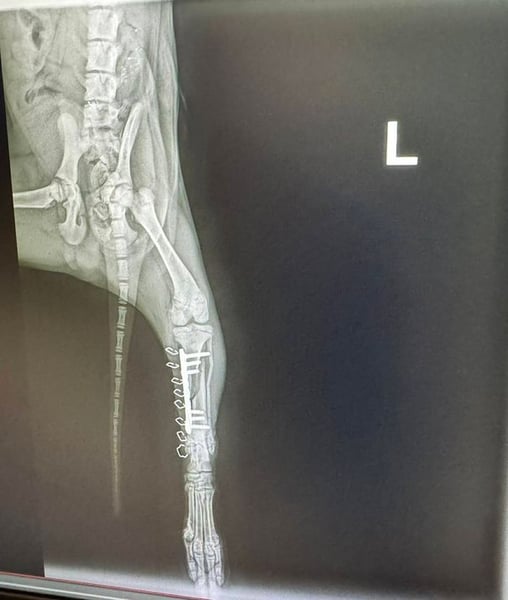

Bemerkungen: Hubsi wurde von einem Auto angefahren. Er hatte ein gebrochenes Hinterbenchen. Dieses wurde erfolgreich operiert.

Hubsi ist ein sehr lebhafter und verspielter Welpe und seit Mitte März 2026 in unserem Partnertierheim. Er kam zu diesem Zeitpunkt direkt aus der Tierklinik, denn er wurde in der Nähe einer Romasledlung von einem Auto angefahren und erlitt einen Bruch des Hinterbeinchens. Er wurde natürlich operiert und erholt sich momentan bei der Tierheimleitung im Wohnhaus.